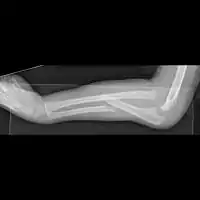

X-ray of Monteggia fracture of right forearm | |

The Monteggia fracture is a fracture of the proximal third of the ulna with dislocation of the proximal head of the radius. It is named after Giovanni Battista Monteggia.[1][2]